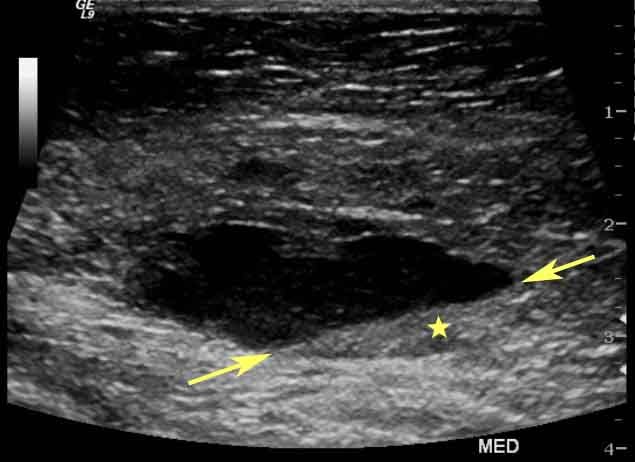

2. Tumores

Uno de los hallazgos más importantes en una tomografía es la presencia de tumores. Los tumores pueden aparecer como masas de tejido anómalas con diferentes características según su tipo y ubicación. Los radiólogos observan detalles como la forma, tamaño y densidad de estas masas para ayudar a determinar si son benignas o malignas. Sin embargo, para confirmar si un tumor es canceroso, a menudo se requieren pruebas adicionales, como biopsias o estudios de imagen más avanzados.

Las infecciones profundas o las inflamaciones de los órganos internos, como los pulmones o los riñones, a menudo pueden observarse en una tomografía. Las infecciones pueden provocar cambios en la densidad de los tejidos, lo que permite a los radiólogos identificar áreas afectadas. Los informes también pueden señalar la presencia de abscesos o líquido acumulado, que indica una posible infección.

6. Problemas abdominales

La tomografía abdominal es fundamental para identificar afecciones como cálculos renales, enfermedades del hígado, apendicitis y trastornos digestivos. La TC permite observar el abdomen en detalle, destacando problemas en los órganos internos y ofreciendo información sobre el tamaño, la forma y la función de estos órganos.